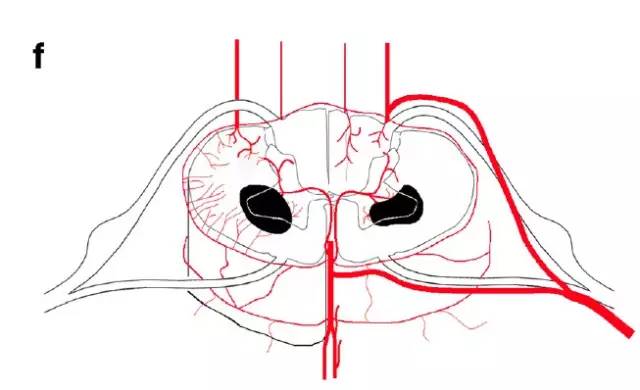

图f,脊髓前角内外系统之间的分水岭区梗死(蛇眼征)